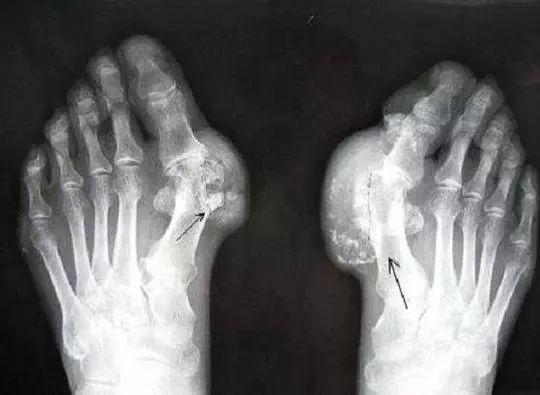

4、痛风石和慢性痛风性关节炎期

尿酸浓度长期升高而未经合理治疗的患者,可导致关节疼痛、畸形、活动受限,甚至使皮肤破溃形成瘘管,增加感染的风险。